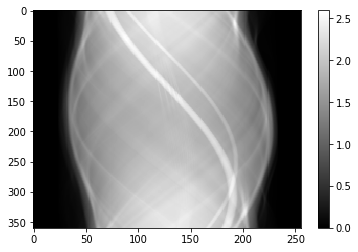

3

4

5

6

sinogram0 = radon(img, theta=theta, circle=True, preserve_range=True)

#sinogram0[100] = (sinogram0[99] + sinogram0[101]) / 2

#sinogram0[100] *= 0.9

plt.imshow(sinogram0.T, aspect='auto')

plt.colorbar()

1

<matplotlib.colorbar.Colorbar at 0x7fce56d6cd60>